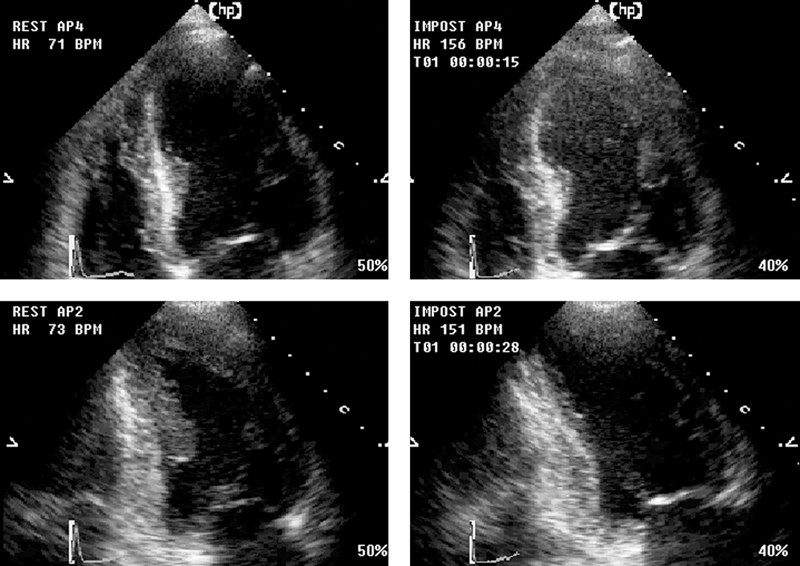

فحوصات تشخيصية لبعض امراض القلب والشرايين التاجية